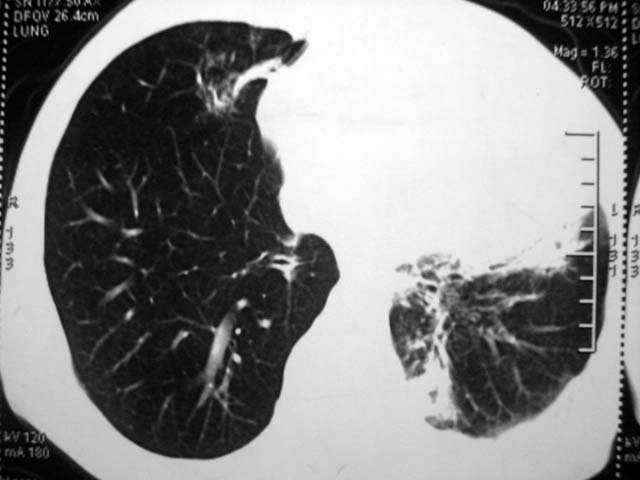

标题: CT17875:肺曲霉菌病?结核? [打印本页]

标题: CT17875:肺曲霉菌病?结核?

男,52岁,发热2月,糖尿病史。

抗结核治疗irpz方案,血糖未治疗,空腹15.9左右。症状无好转,左胸痛。

复查ct

2、双肺见多发片状及结节状高密度影,大多数病灶中心均见“空泡征”。

结果:两肺继发性肺结核并曲霉菌感染。

谢谢!糖尿病人抗感染治疗的同时不控制血糖,治疗效果不会好。